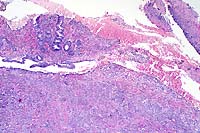

Case 1-1. Kidney. Note tubular ectasia and proteinaceous debris, interstitial lymphoplasmacytic infiltrate, profiles of rhabditiform nematodes, and multinucleate giant cell. 10x obj.

1. Kidney: Nephritis, granulomatous, multifocal and coalescing, moderate to severe, with interstitial fibrosis, tubular ectasia, and many larval and adult rhabditid nematodes, Miniature horse, equine, etiology consistent with Halicephalobus sp.